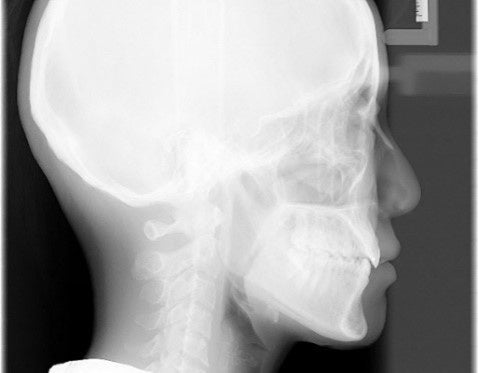

本製品は、上述のパノラマ画像の鮮明さだけでなく、CdTeがもたらす豊富な画像情報をもとに画像の再構成の後に焦点面を自由に変更することが可能であり、次の章で述べるように、日本で初めてパノラマ撮影とデンタル撮影が1台で行え、最先端の画像の鮮明さや低被ばく線量を兼ね備えた革新的な装置として歯科業界で話題となっています。また、セファロ画像についてもCdTe半導体センサーを用いて撮影していることから、従来製品に比べて、軟組織、硬組織がバランスよく観察できると評価されています。

セファロ画像例